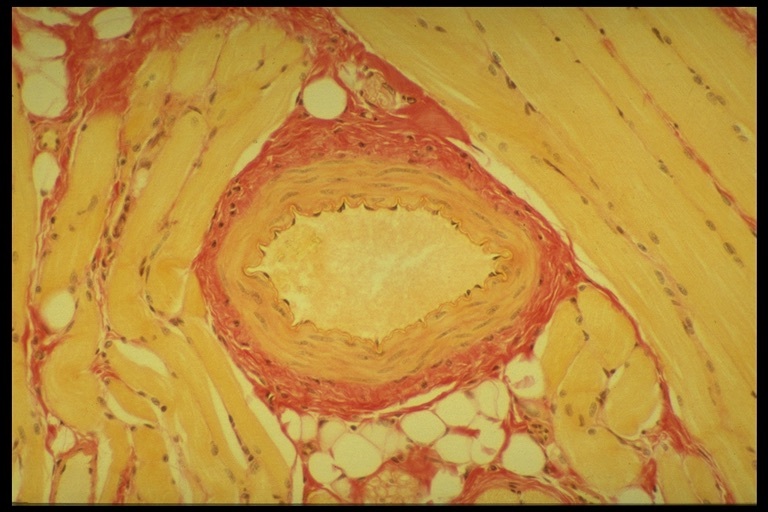

Q

Identify the tissue type

A

Epithelial tissue

Simple epithelia

Blood vessel